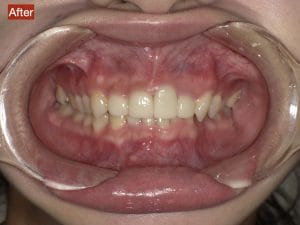

Case034

広島からの患者様です。

前歯を綺麗にしたい。インプラントをしたい。

という主訴で東京の歯医者をいろいろ調べて当院を選んでくださいました。

毎回、遠い中しっかり通ってくださり、選んで頂けた嬉しさと、その気持ちに応えたいという想いで診療させて頂きました。

前歯はご希望のお色でラミネートベニアでは出せない透明感のあるセラミックに上下左側7はインプラントをさせて頂きました。

左上は破折で温存不可。

骨も少なかったので、サイナスリフトも行い計五回の来院で被せ物を入れさせて頂きました。

左下は前回のクリニックでの埋入位置が深すぎて食べカスも毎回詰まる、セルフメンテナンスではら汚れも取れない。インプラント周囲炎にもなっていたので、一度前のインプラントを除去し、そこから新しくインプラントを埋入し、診療させて頂きました。

インプラント、歯並び、審美歯科にご興味のある方はいつでも相談にお越しください。

担当 理事長 佐藤 悠野